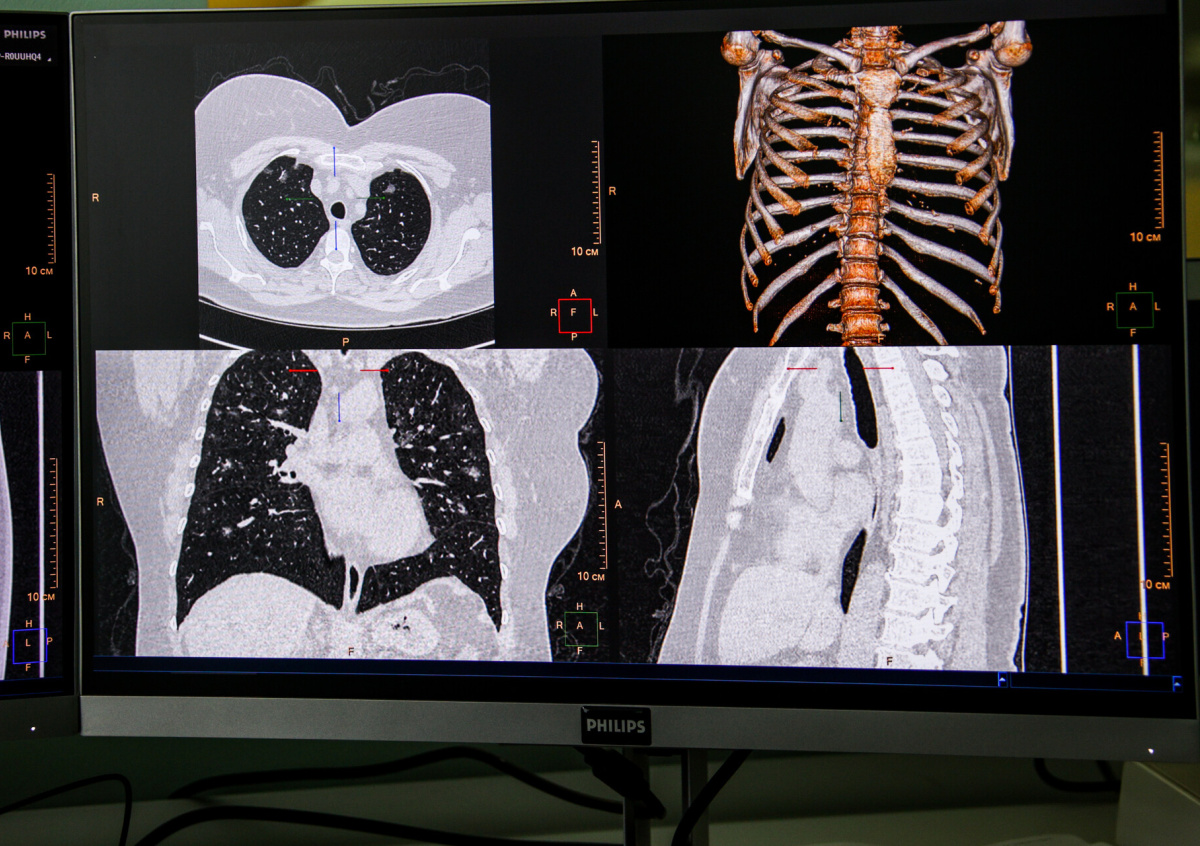

Фото: Сергей Лантюхов/NEWS.ru